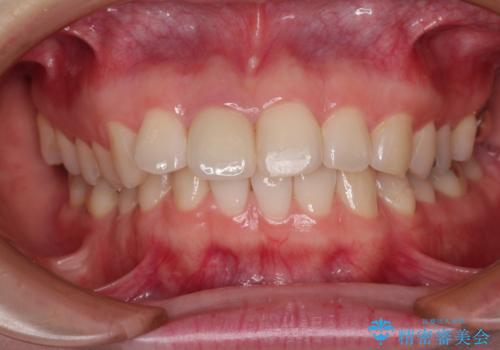

根管治療された状態に大きな問題はなかったため、土台を植立し、オールセラミッククラウンにて補綴治療を行うこととしました。

オーダーメイドタイプのクラウンを選択されたため、周辺の歯と調和が取れる色合いとなるまで修正を繰り返しました。